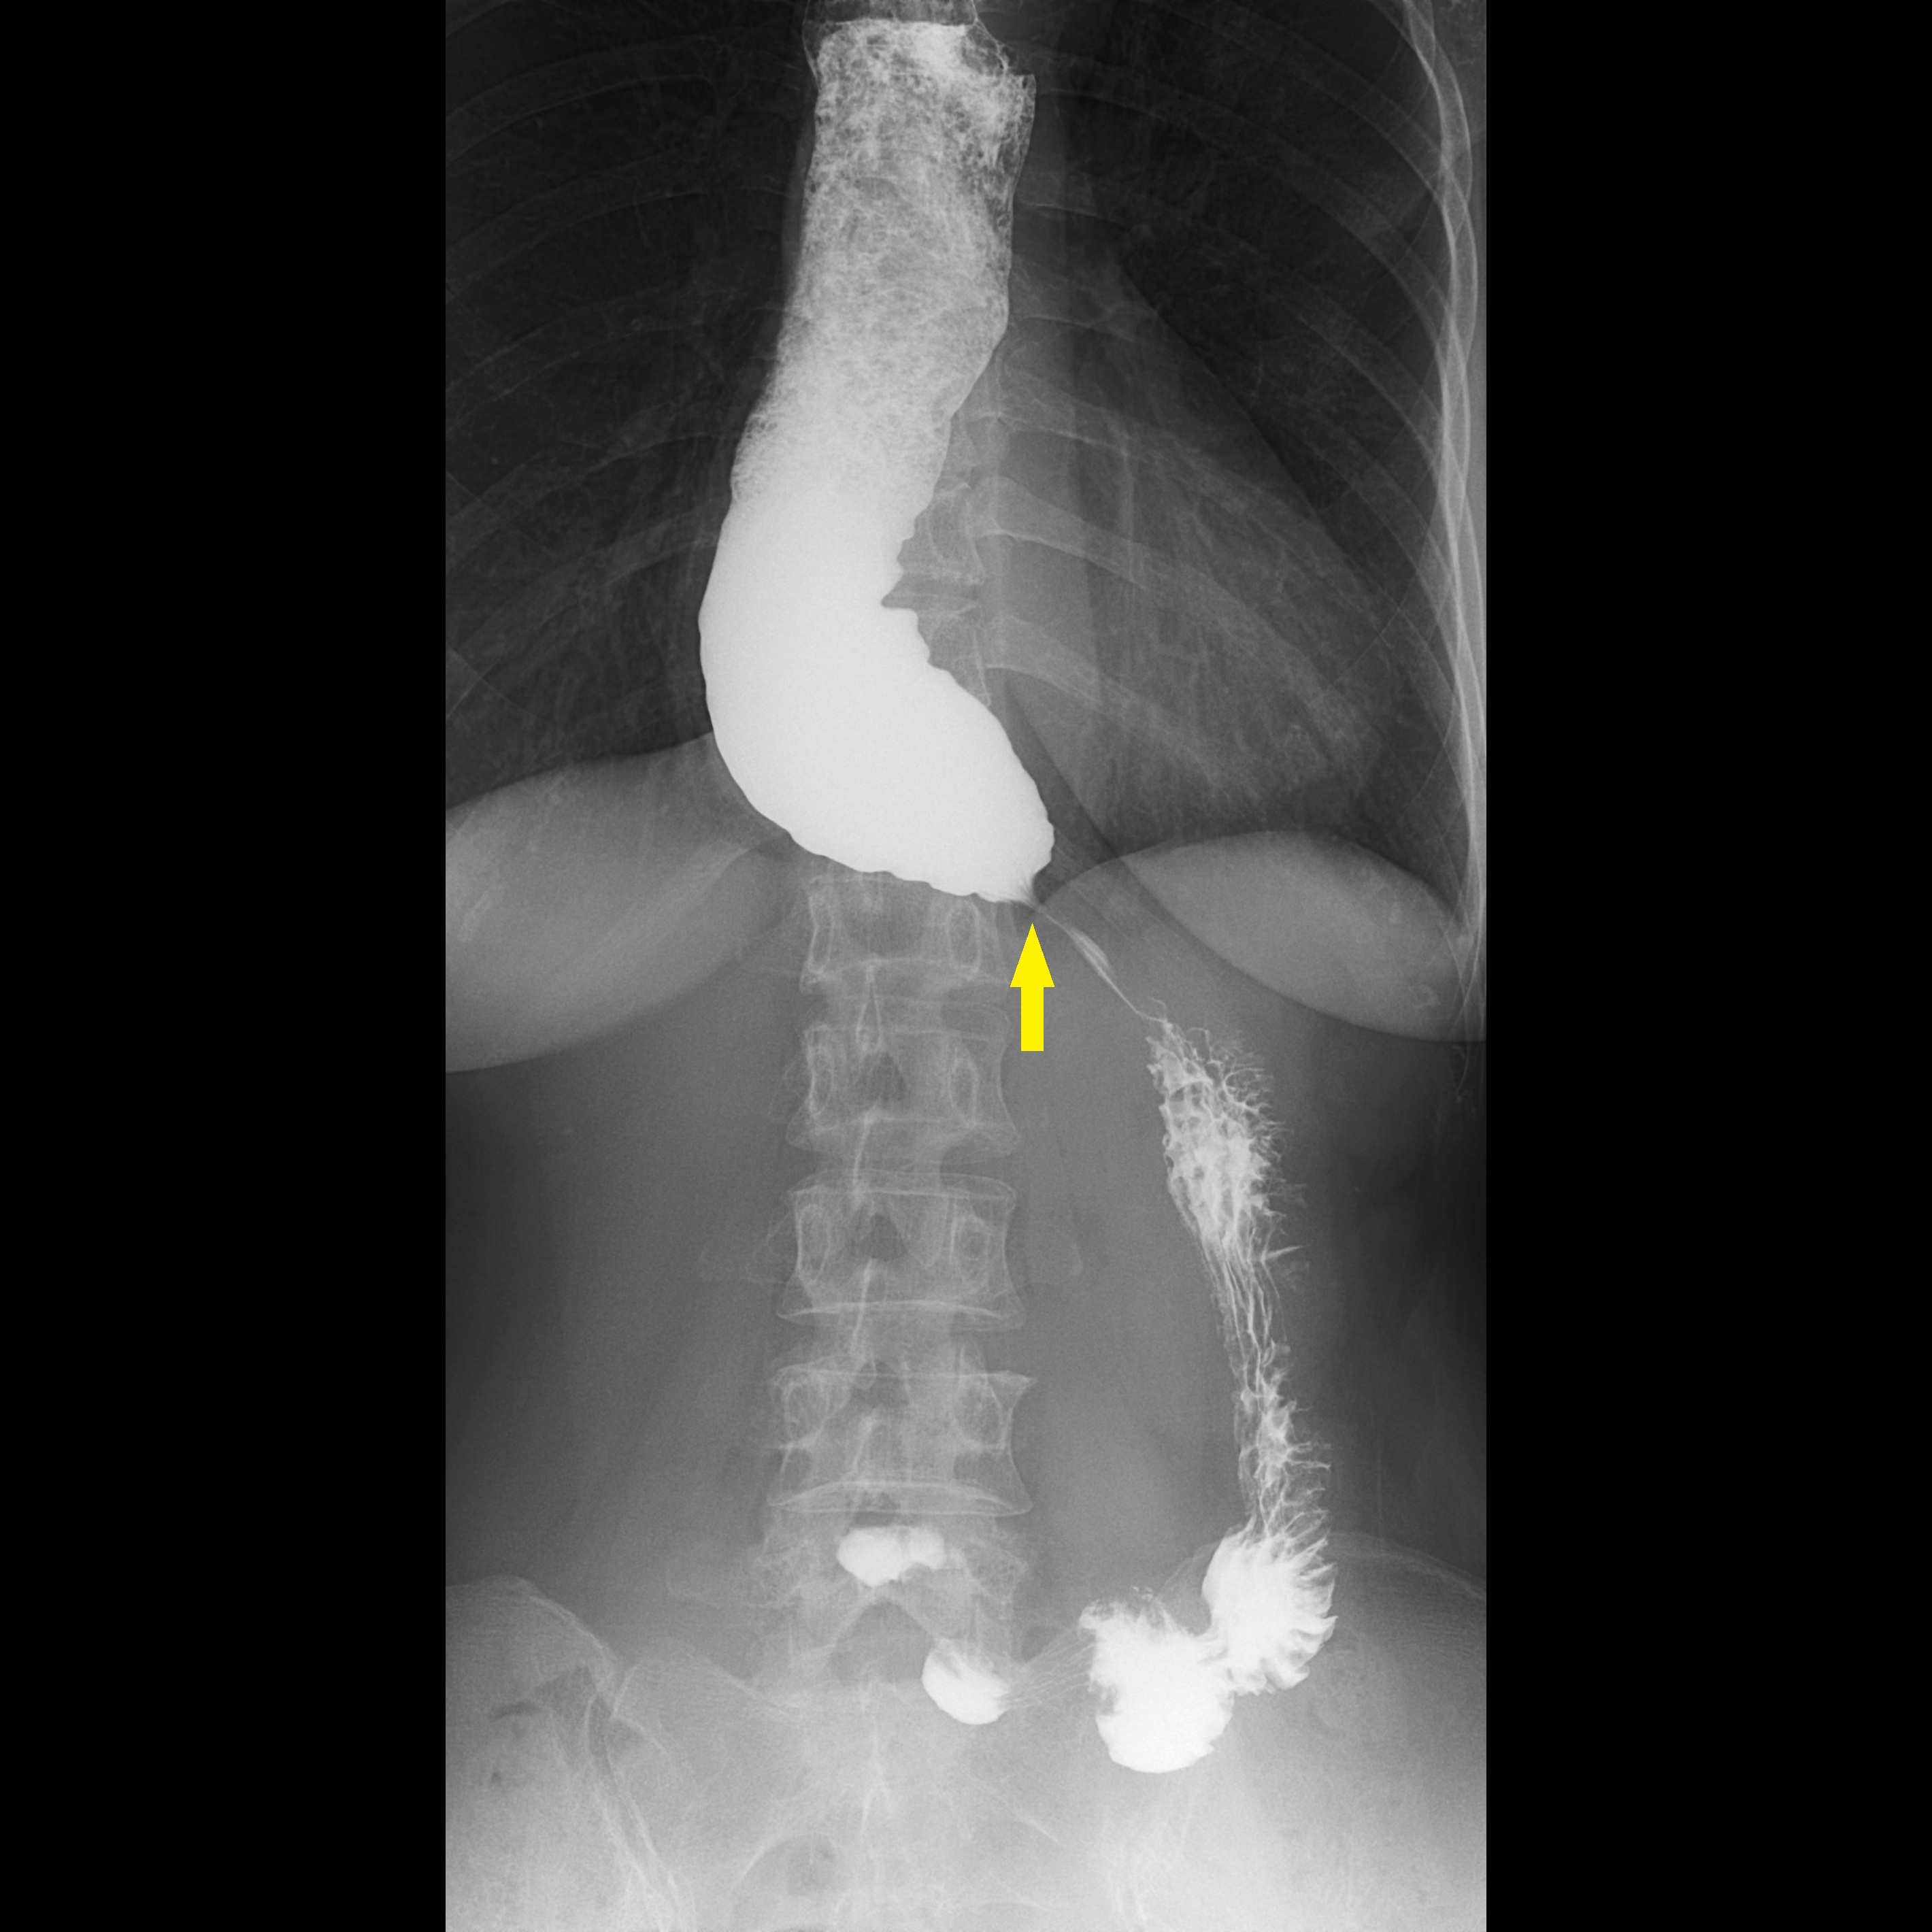

食道攝影及高解析度壓力檢測是臨床上食道弛緩不能症的標準檢查方式。詹崴宇醫師說明,食道攝影雖可觀察顯影劑流速及食道形狀,也能看到典型鳥嘴狀變化,即胃食道交界過緊而使食物過不去,造成上方的食道因為積壓而擴張,形成如同鳥嘴般的的狀態,但非黃金診斷標準;食道高解析度壓力檢測則是在病人清醒時做吞嚥測試,觀察食道蠕動波形,藉此觀察吞嚥時的壓力是否正常,雖是黃金診斷準則,但臨床上卻有部分病人的檢測結果不明確,導致無法確診,進行後續治療。台灣近來引進Endoflip,是在病人麻醉狀態下,利用氣囊感測器測量食道的擴張性。正常情況下,食道應該像很有彈性的新氣球,只要稍微給點推力就能撐開;但如果食道的彈性變差了,即使氣囊在裡面用力推,食道也動彈不得,將導致食物下不去。這項檢查能補足傳統「食道壓力檢測」難以判讀的死角,提供更精準的數據;加上是在麻醉狀態下進行,大大降低了病患檢查時的恐懼與不適感。